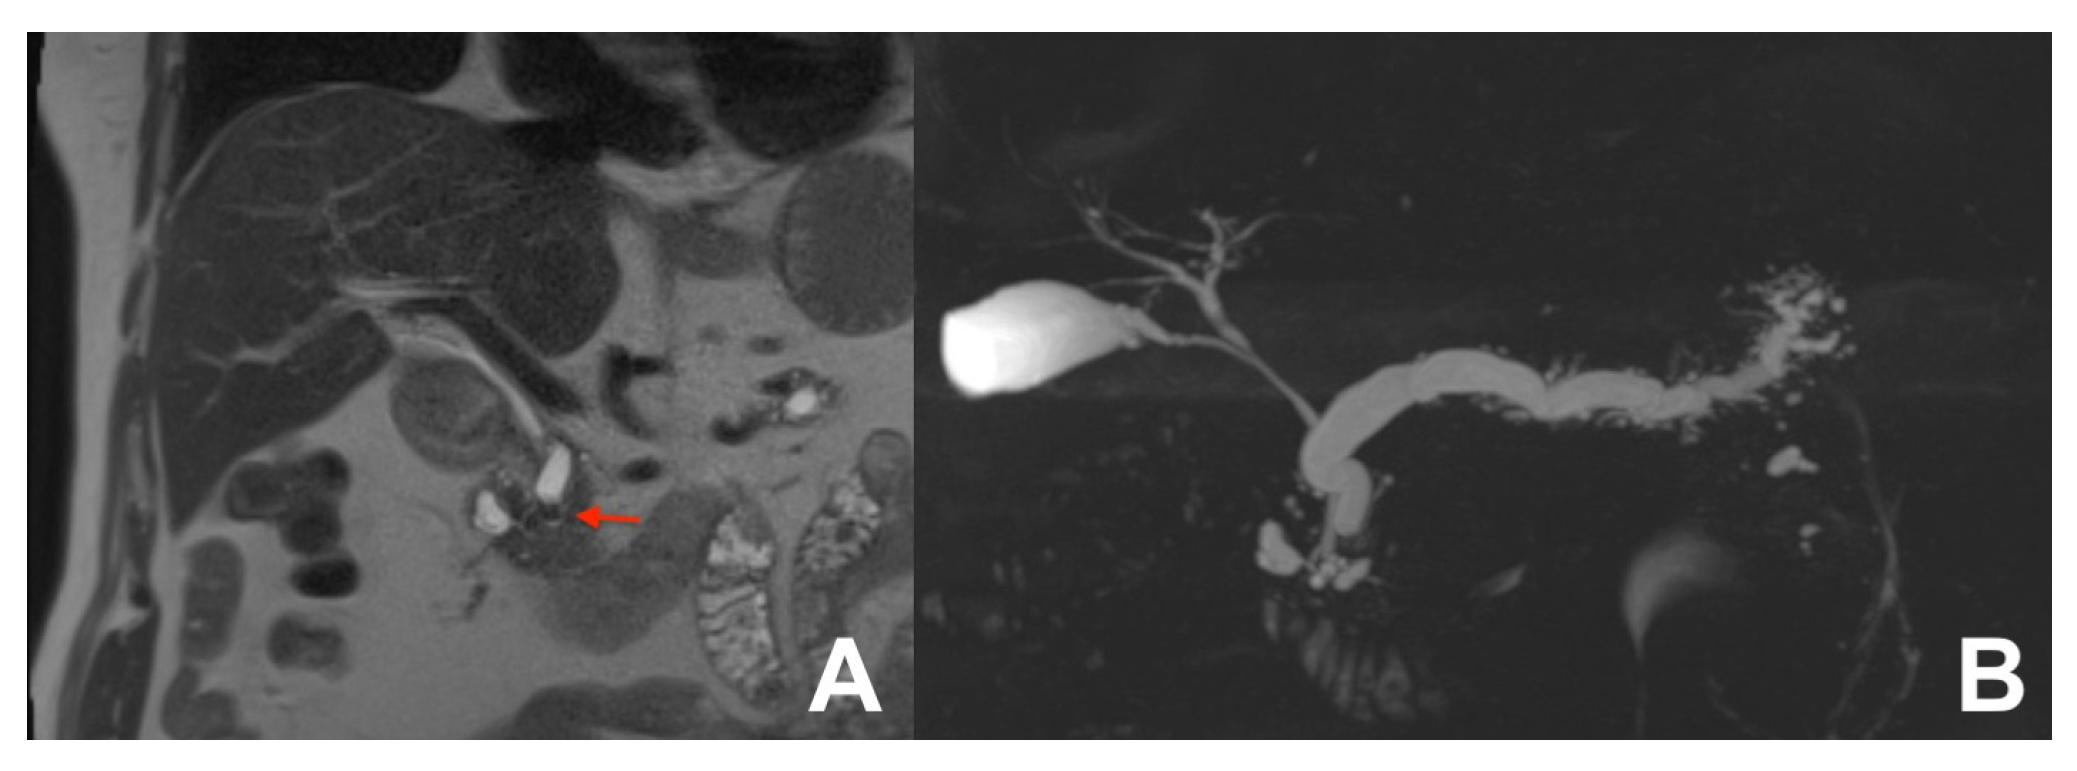

| MRCP 3D | OBLIQUE CORONAL | Biliary anatomy and calculi or stenosis | |||

| MRCP 3D | OBLIQUE CORONAL | -- | -- | use MIP and sub MIP for better detection of calculi | |

| MRCP 3D | OBLIQUE CORONAL | -- | -- | Biliary anatomy and calculi | |

| MRCP 3D/2D | OBLIQUE CORONAL | Anatomy of wirsung duct | ||

| MRCP 2D with secretin | OBLIQUE CORONAL | Functional information | ||

| MRCP 2D with secretin | OBLIQUE CORONAL | For the early diagnosis of CP | ||

| MRCP 2D with secretin | OBLIQUE CORONAL | For the differential diagnosis of pancreatic duct stenosis (“duct penetrating sign”) | ||

| MRCP 3D/2D | OBLIQUE CORONAL | Relationship between the wirsung duct and the cystic lesion | ||

| MRCP 3D/2D | OBLIQUE CORONAL | Comprehensive evaluation of the wirsung duct and cystic lesions | ||